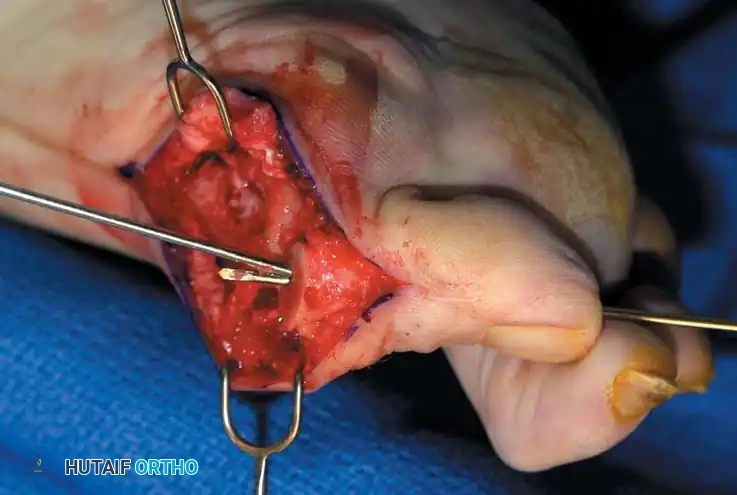

• Using a Freer elevator or a small osteotome for its strength, mobilize the fi bular sesamoid (Fig. 78-31A to C). This may be diffi cult in elderly patients with signifi cant deformity and adherence of the sesamoid to the metatarsal head. Lift the metatarsal dorsally for exposure (Fig. 78-31D and E).

• When the intersesamoid ligament is incised, grasp the sesamoid fi rmly with forceps or a small Kocher clamp, fl ex the toe at the interphalangeal and metatarsophalangeal joints to relax the fl exor hallucis longus tendon, and pull the fi bular sesamoid distally and medially.

• With release of the intersesamoid ligament, the medial surface of the fi bular sesamoid is free from soft tissue. Distally, the sesamoid is free because of resection of the base of the proximal phalanx. This leaves two sides of the sesamoid, distal and medial, free of soft tissue.

• While pulling the sesamoid distally and medially, use a small blade to incise along the lateral margin of the sesamoid under direct vision. Keep pulling the head of the metatarsal dorsally and holding the hallux distracted and in fl exion. This greatly aids in identifi cation of the margins of the fi bular sesamoid, particularly laterally and proximally.

• The most diffi cult part of the sesamoidectomy and that which should be done last is release of the proximal lateral corner of the sesamoid where the fl exor hallucis brevis lateral head inserts. While incising the lateral capsular attachments to the sesamoid, do not bury the blade of the knife because the neurovascular bundle to the lateral side of the hallux is just lateral to the capsule.

• Now all attachments to the fi bular sesamoid have been removed except the lateral head of the fl exor hallucis brevis, which inserts on the proximal lateral margin of the sesamoid. This is a diffi cult section to remove; however, this section can be released under direct vision by pulling the sesamoid distally and medially and lifting the metatarsal head dorsally with a strong two-toothed retractor.

Fig. 78-31 Excision of fi bular sesamoid in modifi ed Keller procedure. With base of proximal phalanx removed and medial eminence excision, exposure of fi bular sesamoid is not as diffi cult from medial incision. A, Operative photograph showing elevation of fi rst metatarsal with strong two-tooth retractor and use of small osteotome to mobilize fi bular sesamoid and lateral capsuloligamentous (frequently contracted) structures. Osteotome is between metatarsal head and lateral sesamoid. When mobilization of fi bular sesamoid is complete, entire sesamoid is visible for excision. Note chondromalacia of tibial sesamoid articular surface medial to osteotome. B, Fibular sesamoid has been excised, and lateral capsular structures and conjoined tendon (in forceps) have been released. Neurovascular bundle to lateral side of hallux is adjacent to these structures. C, Diagrammatic representation of modifi ed Keller procedure. By excising fi bular sesamoid, valgus moment of conjoined tendon of fl exor hallucis brevis and adductor hallucis no longer pulls fl exor hallucis longus tendon laterally (carrying hallux with it) through capsulosesamoid plantar plate and pulley system. D, Metatarsal head must be lifted dorsally to excise fi bular sesamoid under direct vision. E, Note exposure of fi bular sesamoid after mobilization of metatarsal head. Continued